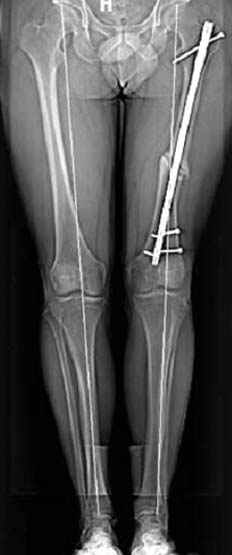

N3 рисунок окончательный снимок, после операции моя рентгенограмма должен выглядеть примерно как эта картина. На N4 снимке клин перед удалением; N5 послеоперации 3 нед.; N6 окончательная рентгенограмма.

Отправитель: Djoldas Kuldjanov 23 Ноябрь 2004, 18:21

пластическая модель; и коррекция бедра аппаратом Илизарова.

Имею другие снимки тоже, получится как отчет о моей работе.